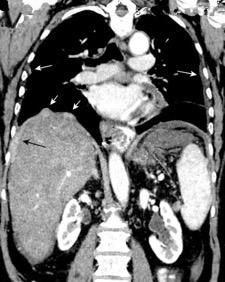

Empiema pleural secundario a carcinoma de la flexura esplénica (masa visible)

Lian R et al. Empyema caused by a colopleural fistula. Medicine (Baltimore) 2017/Osada T,, et al. Thoracic empyema associated with recurrent colon cancer: report of a case and review of the literature. Dis Colon Rectum 2001